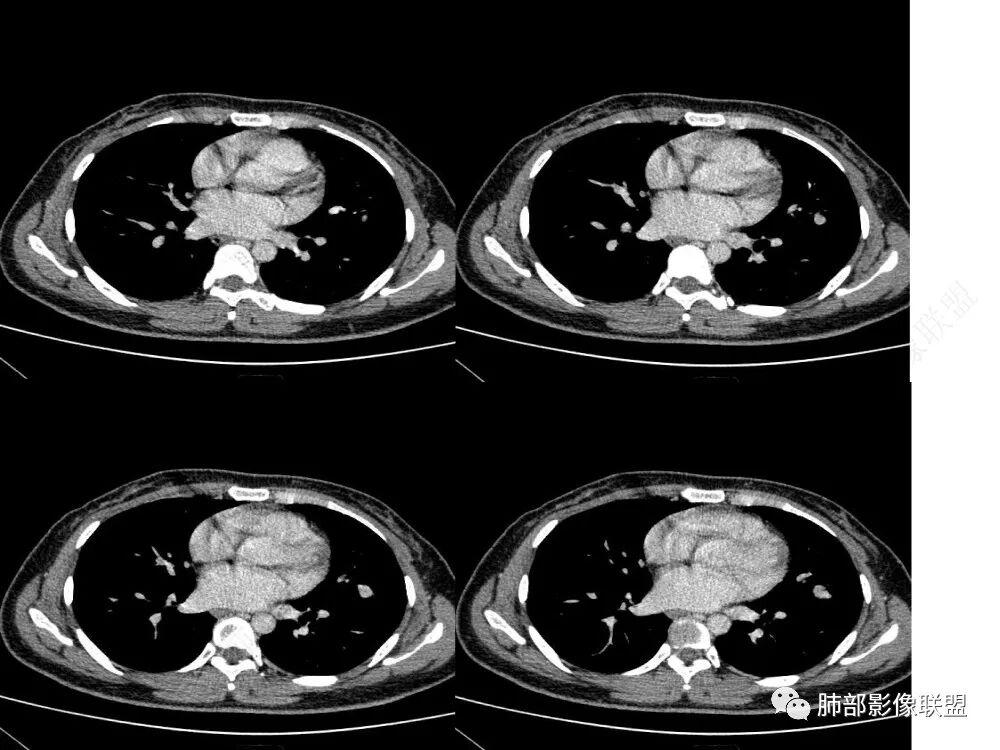

1、临床特点:30岁女性,体检发现肺部结节。

2、影像特点:左肺上叶舌段实性密度结节,边界清楚,略呈不规则三角形,边缘多平直,未见分叶、毛刺及明显收缩。密度均匀,未见钙化、脂肪密度或低密度液化空洞,持续渐进强化。未显示相关支气管及血管出入、血管贴边等。未见明确卫星病灶。双肺门及纵隔未见增大淋巴结。

3、病例小结:年轻女性,体检发现,左肺上叶舌段实性结节,边缘清楚光滑,未见分叶毛刺及收缩,亦未见边界清晰的磨玻璃晕,与支气管血管了无瓜葛等,较为符合的是肺良性结节。

1)边缘平直略呈三角形,甚至外围局部凸起,强化方式等都应当排除肉芽肿性炎。

2)形状不规则,强化明显,支气管囊肿性不在考虑之列。

3)边界清楚,未显示相关支气管及血管出入,强化明显,应当想到硬化性肺细胞瘤。

4)未见明显脂肪密度及爆米花样钙化影,强化明显,缺乏常见的错构瘤征象。

5)形状不规则,强化明显,类癌应当警惕。肺门纵隔未见肿大淋巴结,其他神经内分肿瘤可能性较小。

CT:形态:圆形或椭圆形结节,边界清楚,无分叶及毛刺、无胸膜凹陷征及血管集中等恶性征象,无卫星病灶,周围无纹理增多及粘连等;大小:平均直径3cm,从<1cm到>10cm均有报道;密度:均匀、软组织密度,偶有出血、囊变、钙化;强化方式:多为均匀明显强化,少数不均匀强化;其它特殊征象:血管贴边征 、空气半月征 、晕征,偶见纵隔淋巴结肿大。

小结:硬化性肺细胞瘤(PSP),是肺泡至终末细支气管的错构。男女比约1:5,有两个重要特征:血液灌流和硬化,组织学上还有乳头状区,瘤体里面没有正常形态的肺动静脉及支气管通过,影像主要依据是整体圆球形,没有收缩力,血管支气管贴边,空气半月征。